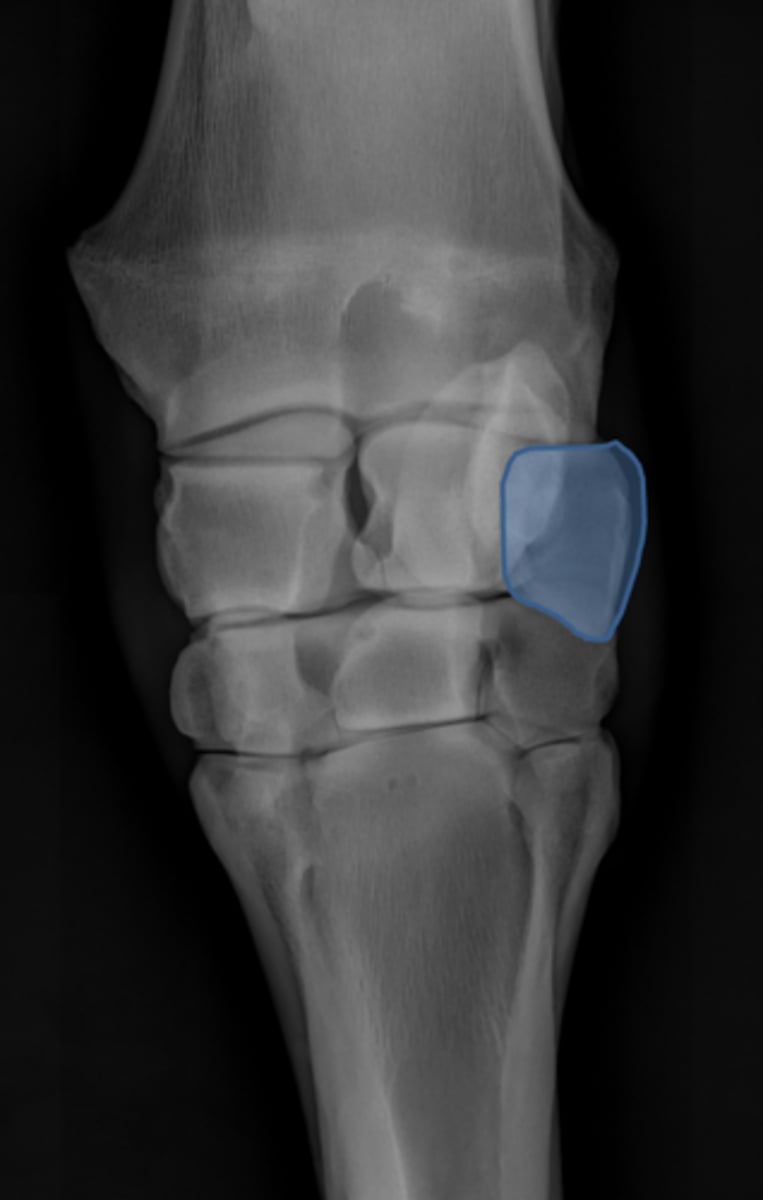

Carpus, DP

ID joint and view

Accessory carpal bone

Radial carpal bone

Intermediate carpal bone

Ulnar carpal bone

Second carpal bone

Third carpal bone

Fourth carpal bone

Second metacarpal (medial splint)

Third metacarpal

Fourth metacarpal (lateral splint)